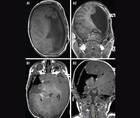

Challenge Case Report: New Onset Seizures

Ashir Bansal, BA; Matthew Tate, MD, PhDAshir Bansal, BA; Matthew Tate, MD, PhD - Epilepsy & Seizures